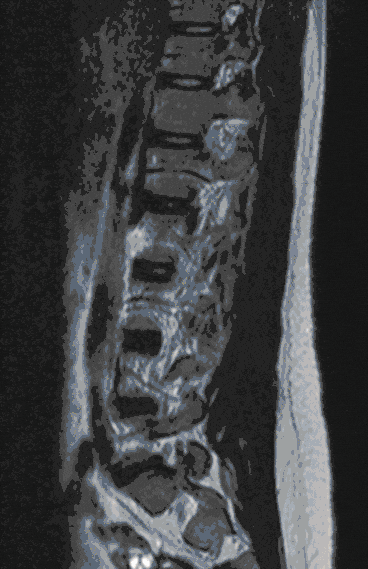

Herniated Disc

Herniated discs are among the degenerative spinal diseases and frequently occur in the lumbar and cervical spine, less frequently in the thoracic spine.